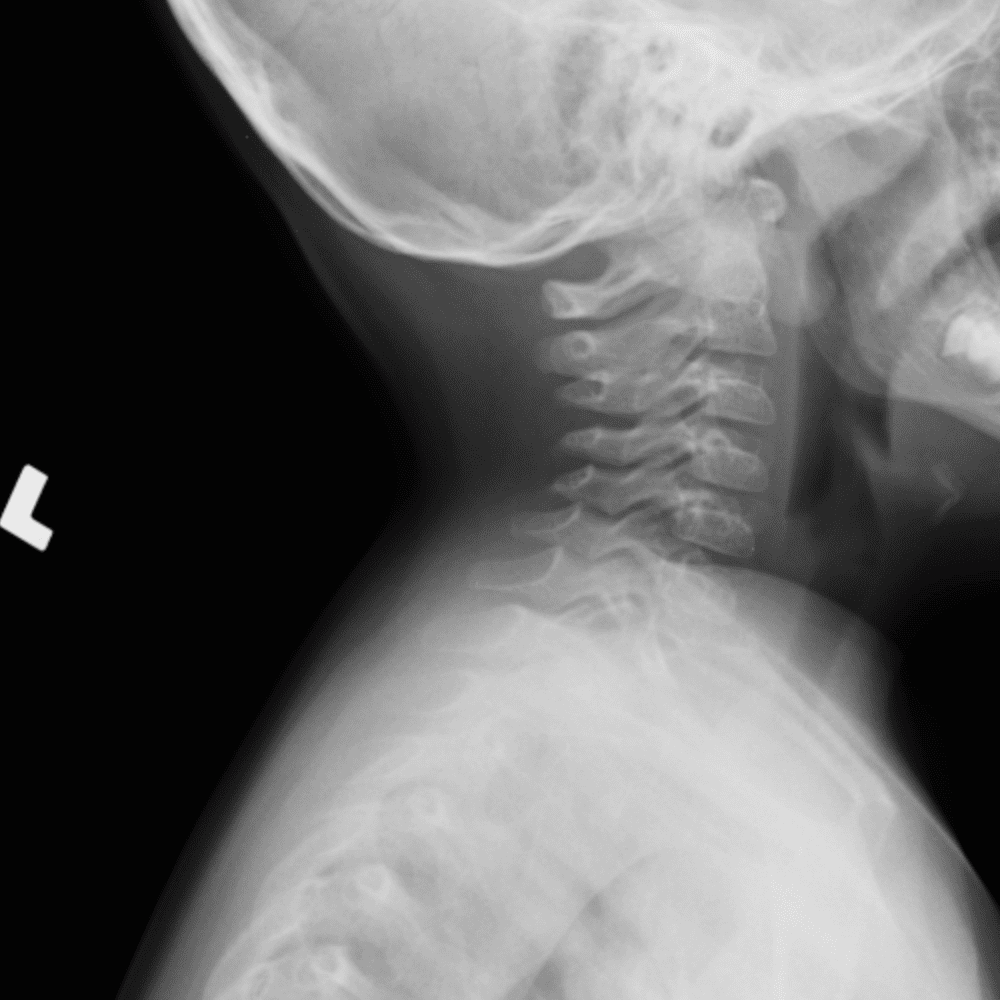

Peds Chest

Practice

Simulates call by including subtle or difficult cases and some normals.

50 cases